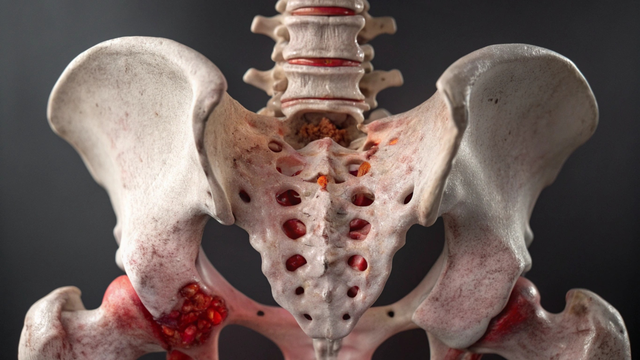

Gãy xương